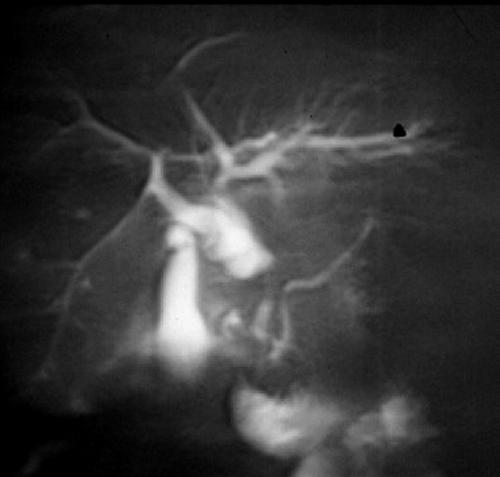

Accurate preoperative imaging evaluation of the degree of local tumor extension and peripancreatic vascular involvement are among the most important factors for predicting the likelihood of success from surgical resection and the prognosis in patients with a malignant pancreatic neoplasm. The accepted criteria for surgical resectability include [9]: tumors (<2 cm) with intact margins and without vascular involvement or metastasis. In this context, despite the fact that CT and MR show a high positive predictive value (88%), they both have a low negative predictive value (23%) [10]: in other words, if CT and MR easily determine unresectability, a large number of neoplasms judged potentially resectable on the basis of imaging findings prove not to be surgically resectable in the operating room. The limits of imaging can be summarized as follows: 1) poor sensibility to detect small metastases in the liver (<2 cm); 2) poor detection of metastasis localized on the hepatic surface; 3) poor detection of peritoneal implants and 4) low sensibility in the detection of vascular involvement particularly when neoplasms are fixed or partially encircle adjacent vessels. Since laparoscopy is the gold standard for detecting small metastases and peritoneal implants, the goal of imaging techniques is to improve the accuracy of vascular involvement. By using a biphasic dynamic MR technique, optimal peripancreatic vascular enhancement can be obtained [5] (Figure 4); in this setting, angio 3D studies do not provide further information when compared to conventional imaging.

Figure 4. Contrast-enhanced RF fast T1-weighted MR images (same case) show pancreatic neoplasm infiltrating the hepatic and splenic arteries at the origin (upper) and the splenic vein (lower). Slight dilatation of the main pancreatic duct is also visible (upper).